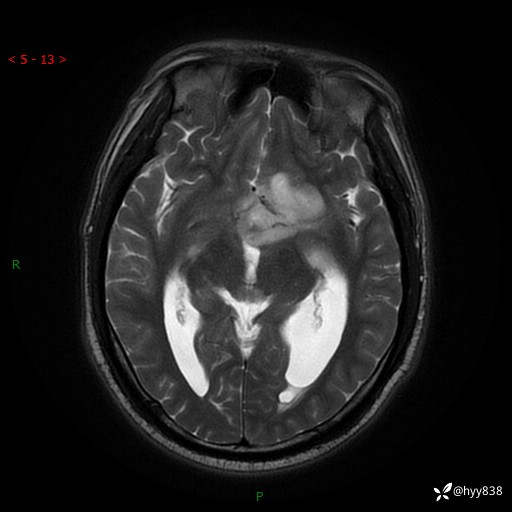

颅脑MRI平扫+增强